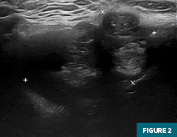

Initial targeted soft tissue ultrasound of the neck at midline demonstrated a 4.6 cm heterogeneous mixed cystic and solid mass at level 1 cervical nodal station (Figures 1 and 2). Subsequent imaging with contrast-enhanced CT of the neck confirmed the presence of a left para-midline enhancing mixed cystic and solid mass with an enhancing mural nodular component. This mass was located slightly inferior to the hyoid (Figures 3, 4, and 5) and was embedded within the strap musculature and clearly deep to the platysma. This mass was concerning for a neoplasm originating from a thyroglossal duct cyst.